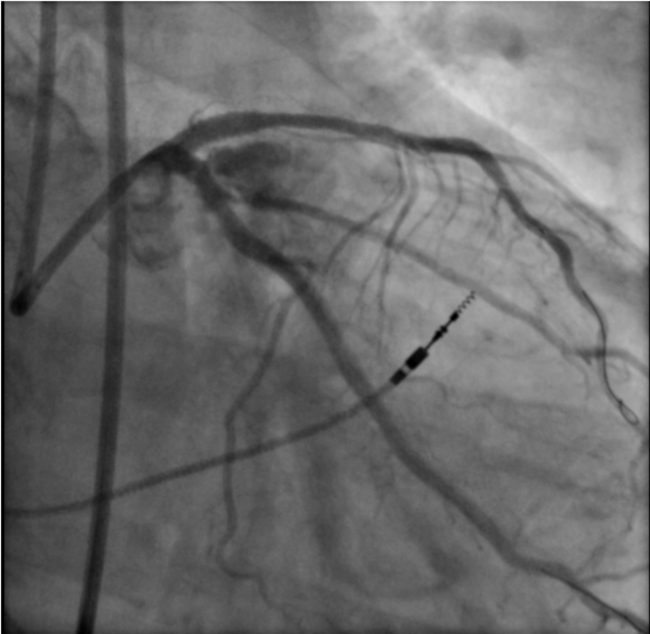

Coronary dissection (46.7%), aortocoronary dissection (26.7%), and coronary perforation (26.7%), including Ellis grade 3 perforations (26.7%), were the predominant indications for emergency cardiac surgery in our cohort. These severe complications can arise suddenly, leading to rapid hemodynamic deterioration through tamponade, myocardial ischemia, or cardiac arrest.19 Our observations parallel those of Darwazah et al, who identified failed angioplasty, dissection, and perforation as the principal drivers of surgical conversion.18 Importantly, while most coronary perforations can be stabilized with covered stents, prolonged balloon tamponade, or pericardiocentesis, a subset remains unresponsive to these strategies and requires immediate surgical intervention.20 An illustrative case from our cohort is shown in Figure 2. This highlights the need for interventional teams to maintain readiness for prompt surgical collaboration when faced with refractory dissection or perforation, as timely escalation can be lifesaving.